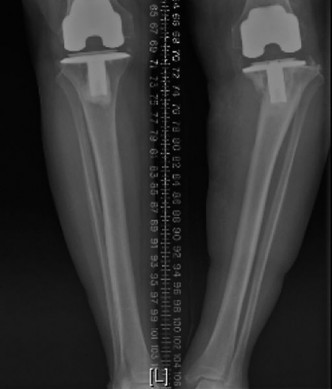

The correct answer is (E). The x-rays demonstrate bone loss with an uncontained tibial defect and loosening of the components. Revision should include stemmed implants to improve fixation and a method to reconstruct the uncontained defect with either porous metal metaphyseal cones (such as Trabecular Metal™ cones), metal augments, or structural allograft. Cancellous graft can only be used in contained defects where there is sufficient cortical bone to contain the defect. In this patient, porous metal cones were used to reconstruct the metaphyseal defect. Cemented stems were used for fixation, and a constrained implant was needed because of collateral ligament insufficiency (Fig. 7–11).

Figure 7–11 painful knee in a patient with history of TKR